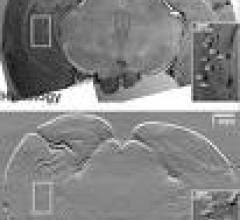

September 23, 2009 - Siemens announced today the sixth annual “New Point of View” Preclinical Image of the Year awards ...